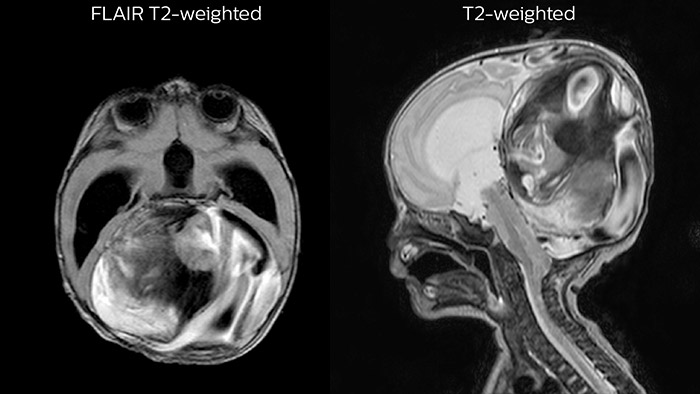

Hydrocephalus post hemorrhagic

Both pictures show a ventriculoperitoneal shunt. With our previous scanner our hydrocephalus protocol needed about 25 min. With Ambition the examination time is about 14 min. including a CSF PCA sequence to show flow in the aqueduct.